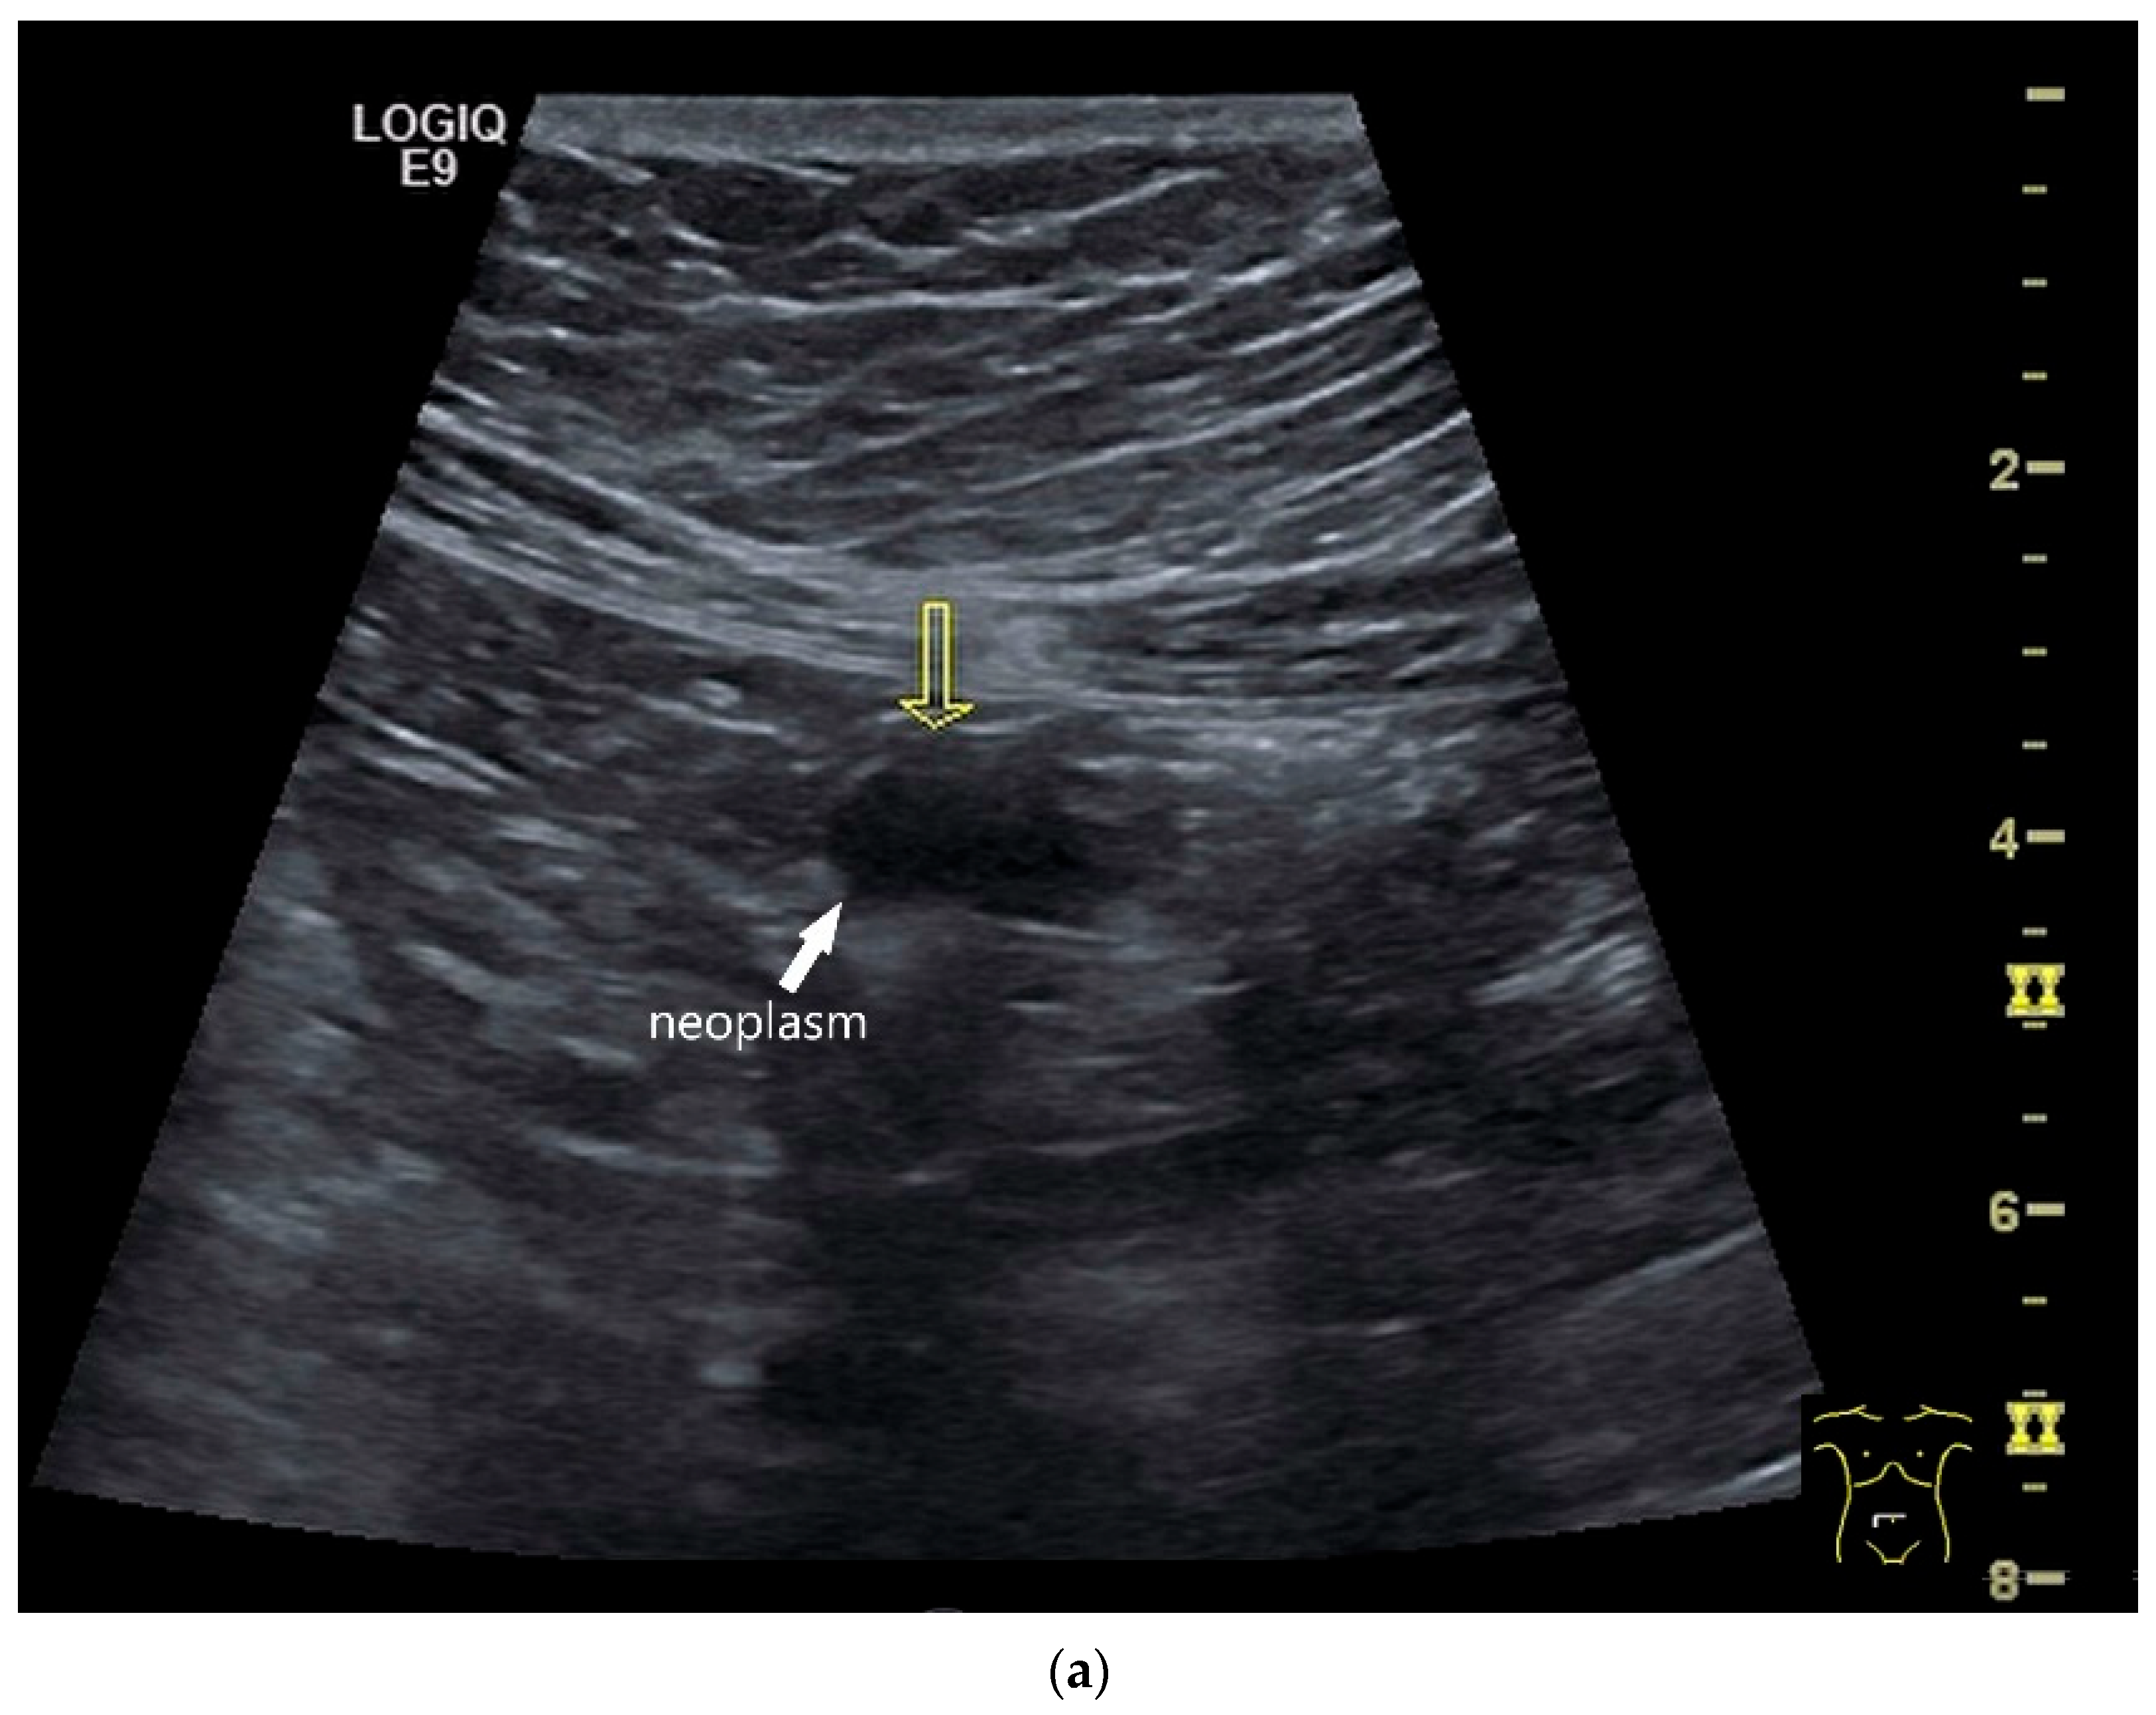

| Neuroendocrine tumor | Small, nodular hypoechoic wall thickenings, mostly in the submucosa with spreading into the other layers. Usually with small vessels on CDI. Regionally enlarged lymph nodes. Multilocular manifestations are possible. |

| Lymphoma | Very pronounced wall thickening with marked hypoechogenicity. Large regional and distant lymph nodes. Look for splenic infiltration. Tumor vessels on CDI and hyperenhancement on CEUS. Heterogeneous hyperechogenicity of the mesentery with walling of the mesenteric vessels. Multiple localizations are possible. |